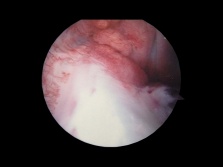

Anterior cruciate ligament seen under arthroscopy

The ACL's higher attachment can be found within the notch of the distal femur while the lower part of the ACL attaches in front of the intercondyloid eminence of the tibia.

The purpose of the anterior cruciate ligament (ACL) is to keep the knee stable, more approximately to resist anterior translation and medial rotation of the tibia, in relation to the femur.